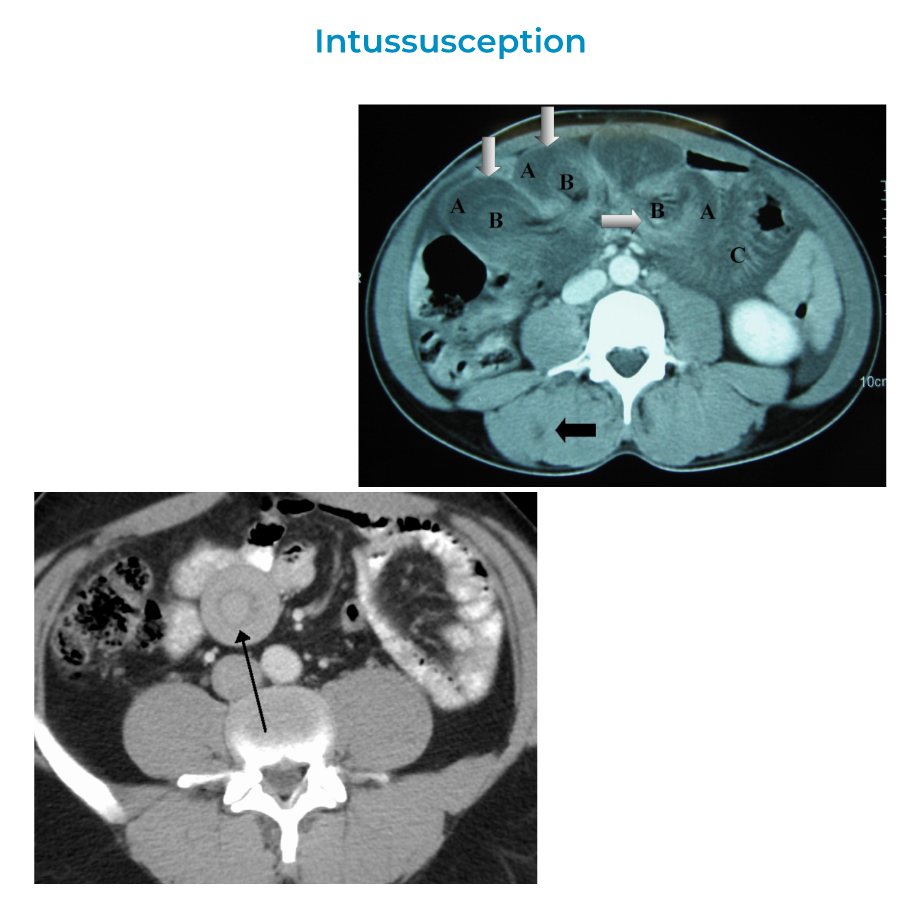

Other structural abnormalities include intussusception, volvulus, and congenital malrotations.

Intussusception